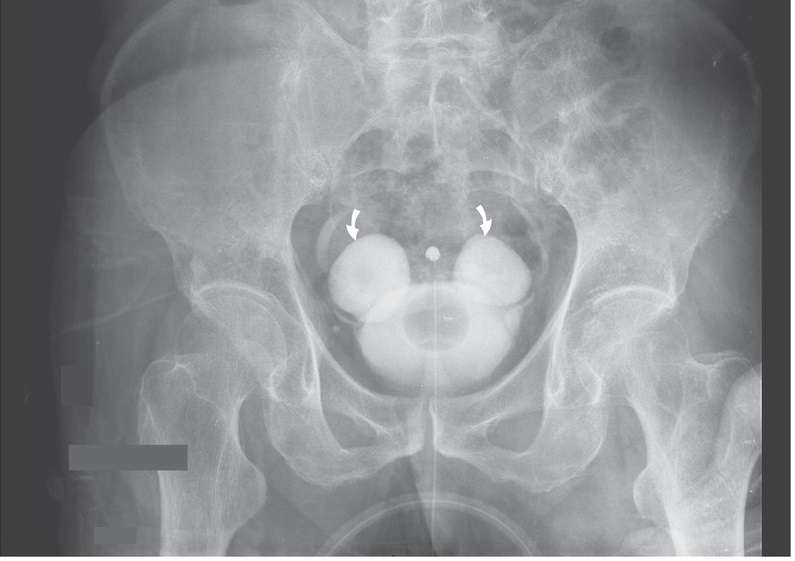

Intravenous urography showed no obstructive uropathy, but symmetric diverticula could be seen near both ureteral orifices (arrows).

These lesions, known as Hutch diverticula, are usually congenital rather than occurring as a result of a neurogenic bladder or an infection or obstruction. They represented a new finding in this patient. Hutch diverticula are more commonly seen in men and boys and are usually unilateral and asymptomatic.